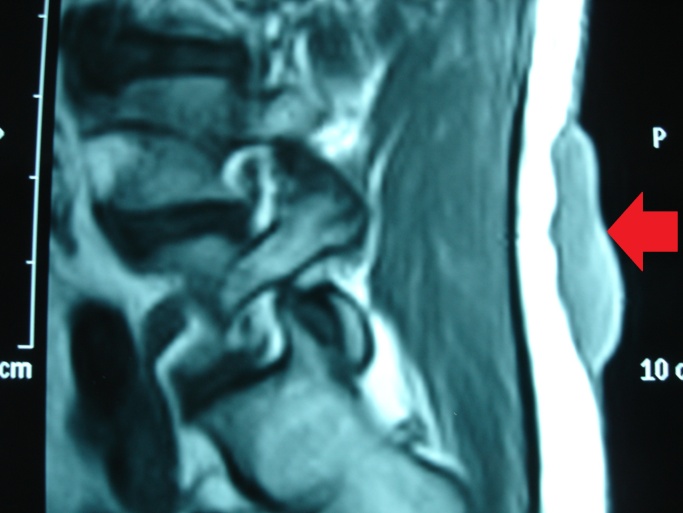

MRI οσφύος — Η βλάβη εμφανώς περιορίζεται στο δέρμα και τον υποδόριο ιστό (Ευγενική παραχώρηση Dr. V. Penopoulos)